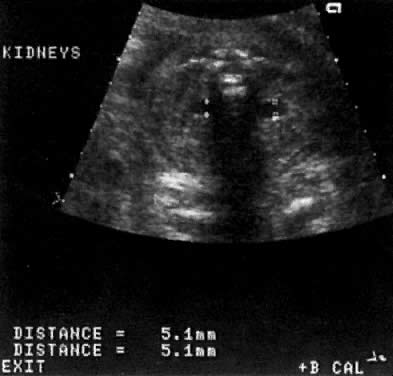

The Ureteropelvic Junction

Dilation of the UPJ (Fig. 14) results from (1) abnormal recanalization of the upper part of the ureter, resulting in varying degrees of obstruction; or (2) absence of the longitudinal muscle fibers in the upper ureter and renal pelvis. In the latter dysfunction, there is abnormal forward propulsion of urine, resulting in a dilation of the UPJ.46 Importantly, dilation of the UPJ may be associated with other anomalies involving the fetal cardiac, gastrointestinal, and central nervous systems.

Fig. 14. A. Cross-section of fetal abdomen at level of kidneys ( spine anterior ) show both kidneys. The left (LT) kidney shows dilation of the ureteropelvic junction (UPJ), but no hydronephrosis is present. B. The fetal spine is tot he left of the echogram and the kidney above the spine also shows dilation of the UPJ, the anteroposterior diameter (calipers) measuring 8 mm. C. The fetal spine is on the right lower side of the echogram. The kidney above the spine shows more severe UPJ (calipers) , with extension to the calyces.

Further, male fetuses are more frequently affected than female (5:1). The UPJ dilation also occurs more frequently on the left side and can be unilateral in 70% of cases.